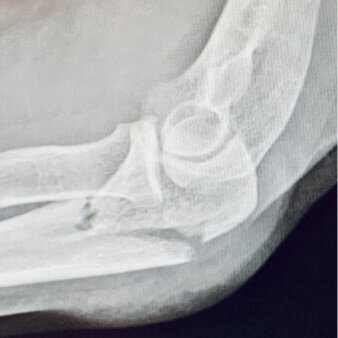

“I have been using the Elbow LOC arm holder for the past several years. It is extremely helpful for my elbow ORIF cases to securely maintain the elbow in position while the patient can remain supine and the entire device is sterile and in the field without needing to be covered with another sterile device.”